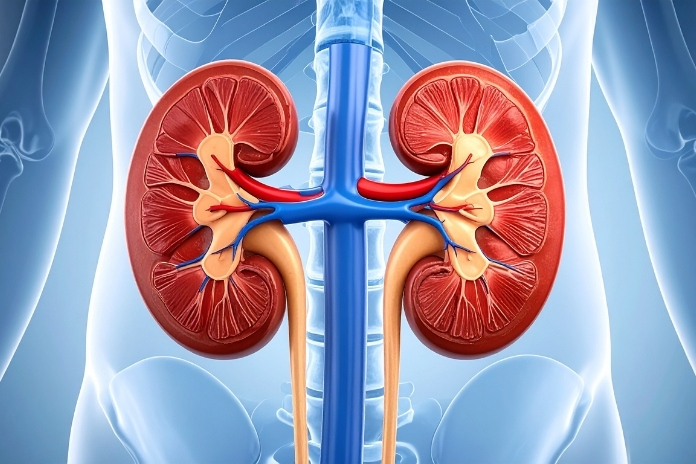

Both conditions stem from complement dysregulation in the kidney’s filtering units, known as glomeruli, but key differences emerge on kidney biopsy. This article breaks down their relationship, differences, and why an accurate diagnosis guides better care.

C3 Glomerulopathy (C3G) is a rare group of kidney disorders driven by overactive complement alternative pathway activity. The complement system is part of the body’s immune defenses, a set of proteins that normally help fight infections, clear debris, and control inflammation. In healthy kidneys, it does its job and switches off.

In C3G, genetic or autoimmune flaws cause uncontrolled C3 protein buildup in the glomeruli, which damages the glomerular basement membrane (GBM), the kidney’s main filtration barrier.

Diagnosis depends on kidney biopsy findings: immunofluorescence shows dominant C3 staining (at least 2+ intensity) with minimal other immunoglobulins. Electron microscopy reveals electron-dense deposits, but their exact pattern varies by subtype. This biopsy-centric definition separates C3G from other glomerulonephritides.

Dense Deposit Disease (DDD), once called membranoproliferative glomerulonephritis type II, features highly specific ultrastructural changes. It arises from the same complement alternative pathway dysregulation as C3G, with C3 fragments depositing in a unique, sausage-like ribbon along the GBM.

These dense deposits transform the GBM into a thickened, rigid structure visible under electron microscopy.